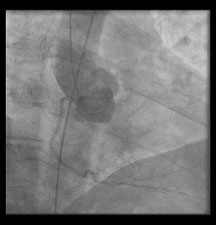

Figure 5: This image is of an aortogram performed via cinematography during left heart catheterization. There is some non-selective filling of the right coronary artery observed during the aortogram in the straight right anterior oblique view, but no sign of an anomalous left circumflex artery. View Figure 5